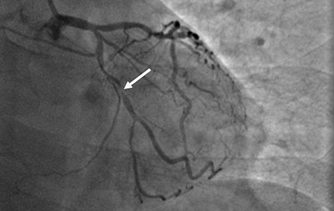

近日,河北醫科大學附屬燕達醫院心血管內三科成功完成一例非常特殊的手術——冠心病三支病變微創介入完全血運重建術。患者李先生冠心病病變極其嚴重,全部三支主干動脈均重度狹窄,各處求診均被告知無法微創介入手術,只能開胸搭橋。拒絕開胸的李先生慕燕達醫院心血管內三科北京安貞醫院專家團隊之名,就診于燕達醫院,由翟光耀主任為其行 “一站式”手術,一 次 性完成三支動脈的修復!手術非常成功,李先生術后恢復良好,滿意出院。   震驚 患者三支血管均90-99%狹窄 ..